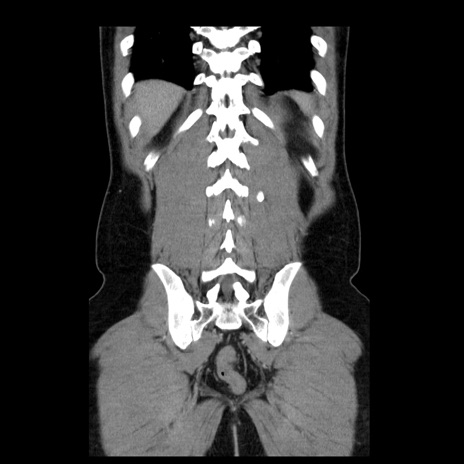

症例4(冠状断像)

横断像